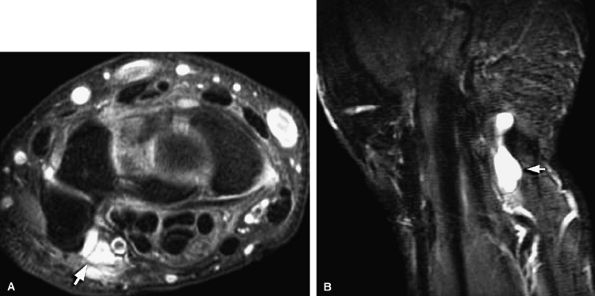

FIGURE 12.50 ● Ganglion cyst compressing the superficial radial nerve. Axial fast spin-echo T2-weighted image (A) and coronal T1-weighted image (B) show a bilobed ganglion cyst (arrows) compressing the superficial radial nerve and radial artery (arrowheads).